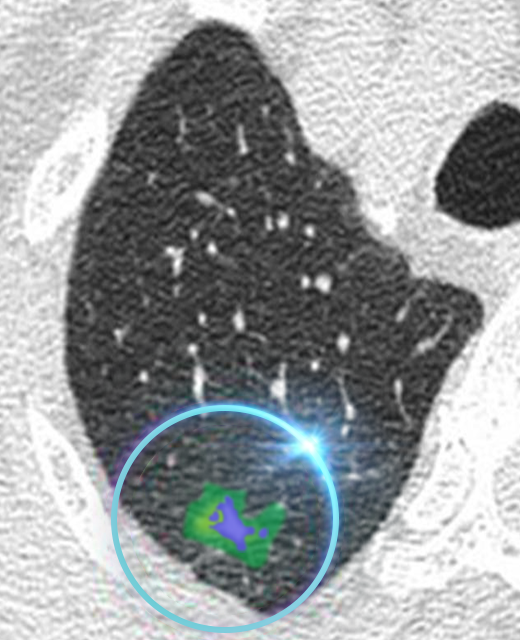

AI Enhanced Ultra Low-Dose Scan

Our AI technology is able to sharpen the quality of the ultra-low dose scan to assist the doctor in early detection.

REiLi is our AI technology that uses deep learning and Fujifilm’s extensive image processing database to detect abnormalities automatically. This helps doctors accurately recognize the affected area and reduce the time taken by radiologists to interpret the scan.

FCT PixelShine is our Deep Learning based image processing software that improves the image quality of low-dose radiation scans. Sharper images have previously only been possible with high doses of radiation. FCT PixelShine enables our machines to produce a sharp, clear image even at ultra-low dose radiation.